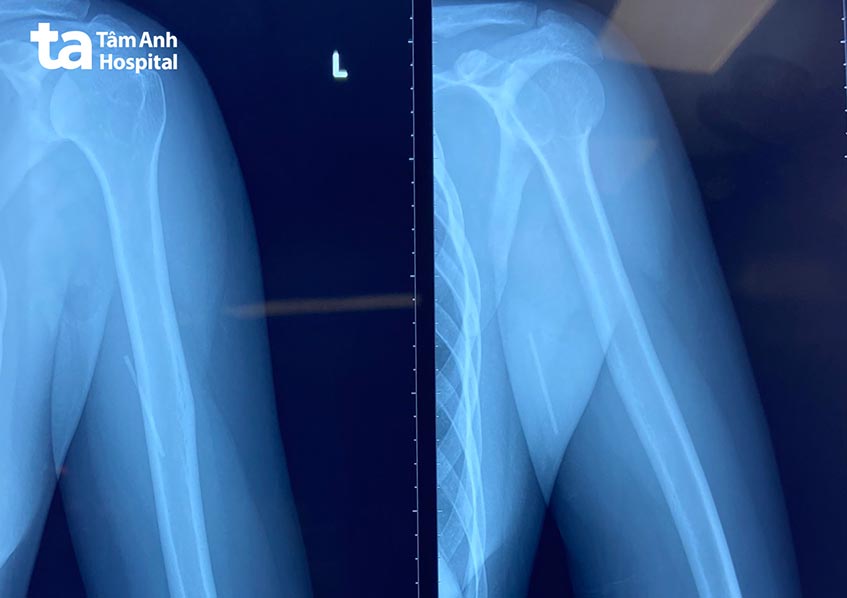

Nhằm xác định chính xác vị trí que tránh thai lạc chỗ, bác sĩ đã sử dụng màn tăng sáng để xác định vị trí của que tránh thai trước và trong phẫu thuật. Nhờ đó, giảm thiểu tổn thương các cơ, mạch máu và thần kinh; mở đường mổ nhỏ nhất có thể, hạn chế sẹo và đảm bảo thẩm mỹ cho người bệnh.

Sau hơn 30 phút can thiệp, que tránh thai dài khoảng 4cm được loại bỏ khỏi bắp tay người bệnh. Hậu phẫu, người bệnh cho biết sức khỏe bình thường, cánh tay cử động tốt, không đau và được xuất viện một ngày sau đó.